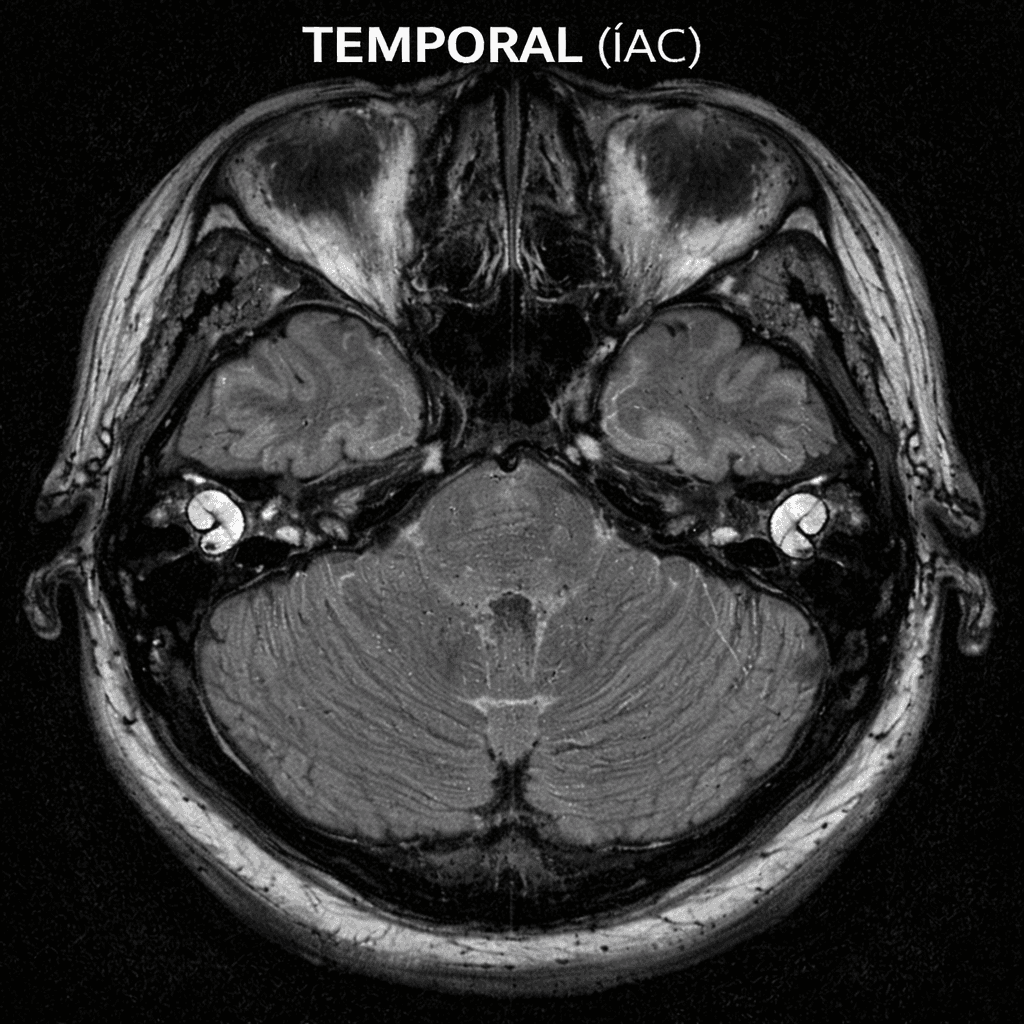

Experience superior MR imaging with Temporal MR! Fast, accurate results. Contact us now for expert radiology services and special check-up packages!

Detailed examination of the middle ear and surrounding bone structures with Temporal Bone CT Scan. Reliable medical imaging center solutions for early diagnosis.